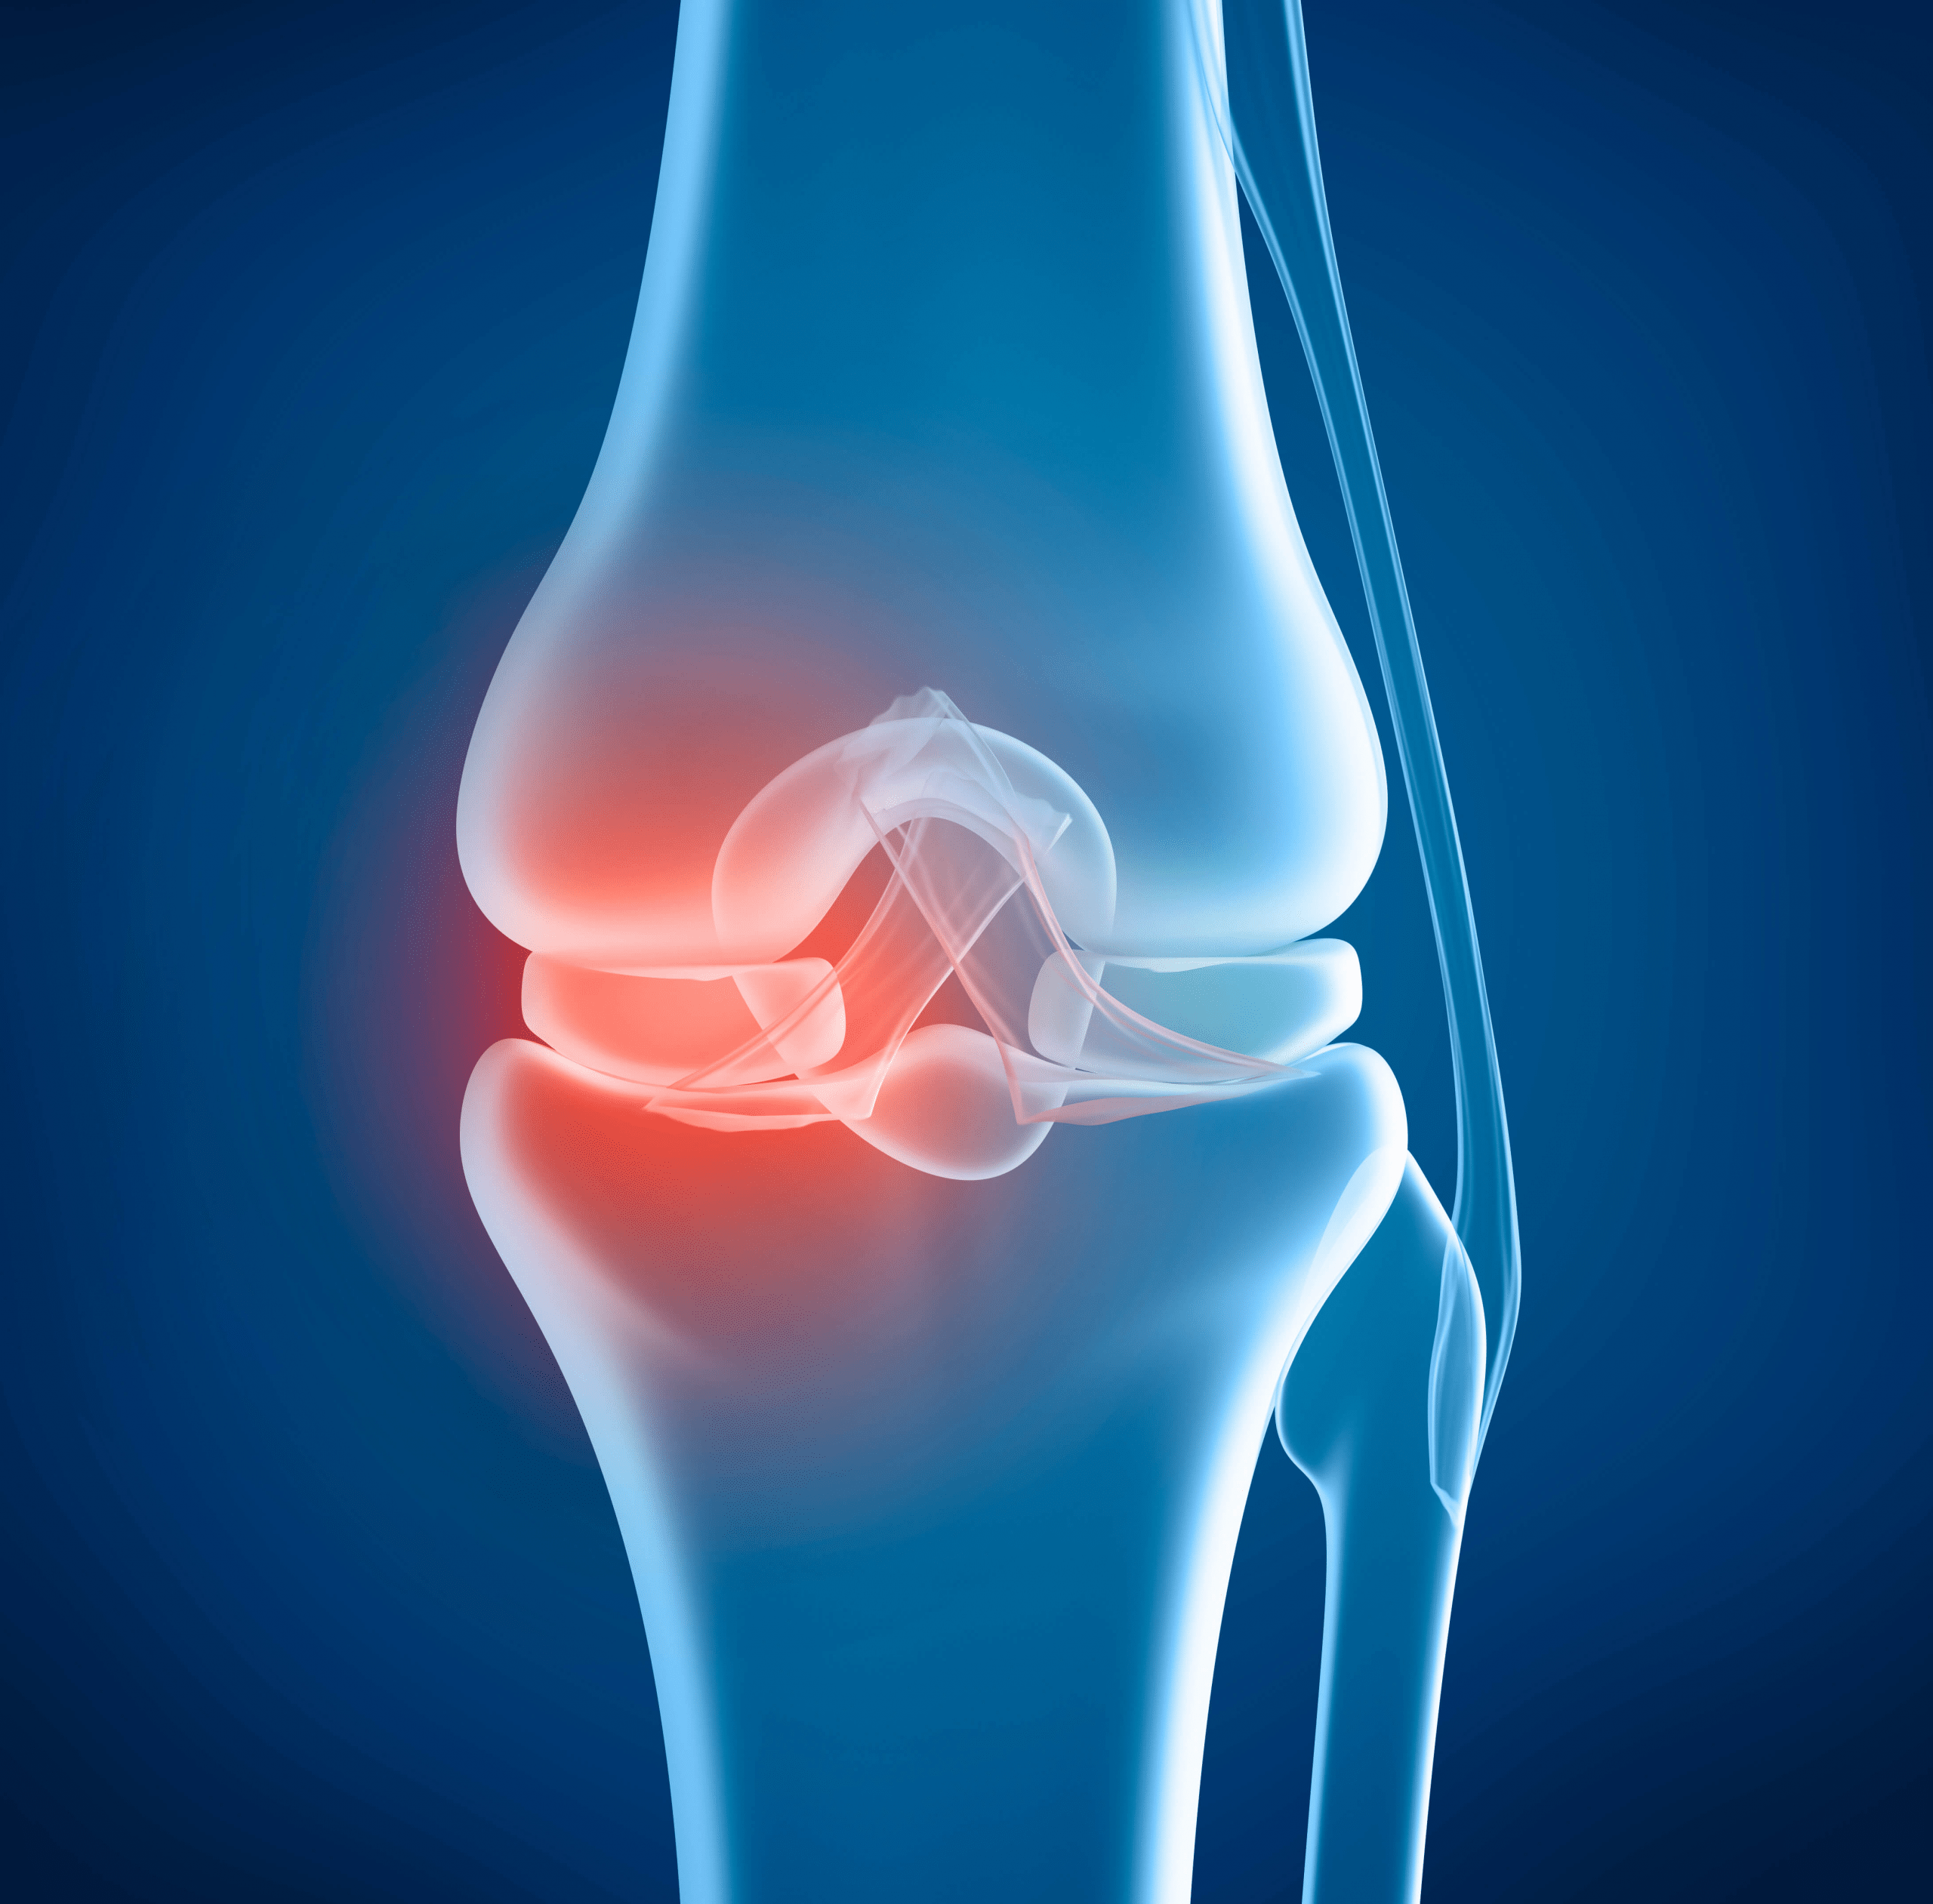

Knee pain affects millions, often sneaking up as we age. It starts with a twinge during walks, then escalates to constant discomfort.

Simple tasks like climbing stairs become daunting. Over time, this can limit your independence and joy in daily life.

But why does this happen? Cartilage wear and inflammation play key roles, leading to that nagging ache.